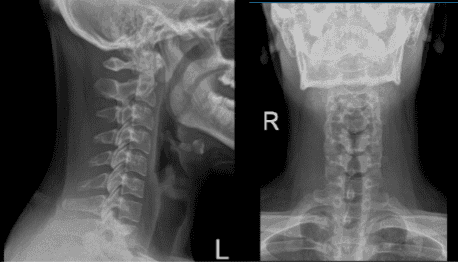

X Ray of Spine and left shoulder were presented during the visit, cervical spine X-ray showed an abnormal straightening cervical curve however left shoulder showed normal radiographs. In this follow up, I advised the patient to continue taking ibuprofen and an MRI will be presented the following week.

Cervical Spine X-ray 2 Views

After a week patient returned with MRI result and showed that cervical spine showed significant result of straightening of the normal cervical lordosis, consistent with an element of muscle spasm and shoulder MRI showed tear of the superior glenoid labrum extending into the anchor the long head the biceps tendon.